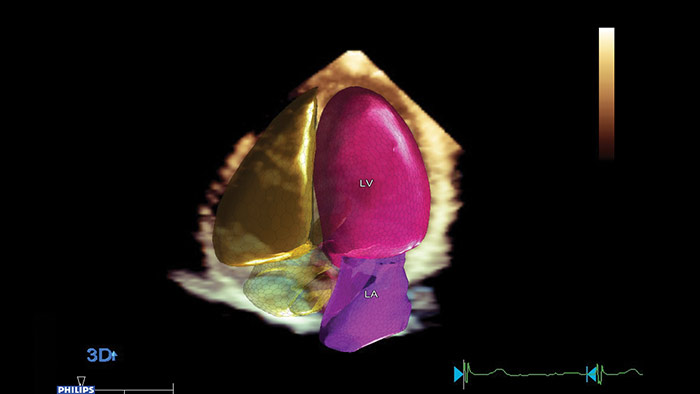

Anatomical Intelligence Ultrasound (AIUS) von Philips, kreiert für eine völlig neue Dimension des Ultraschalls. Mit fortschrittlichen Funktionen für die Organmodellierung, Erstellung von Schnittbildern und zuverlässige Quantifizierung lassen sich Ultraschalluntersuchungen einfach durchführen und besser reproduzieren; gleichzeitig werden aussagekräftige klinische Ergebnisse geliefert, um den wirtschaftlichen und klinischen Herausforderungen der heutigen Gesundheitsumgebung gerecht zu werden.

Zu den Funktionen von AIUS gehören die Automatisierung repetitiver Schritte bis zur kompletten computergesteuerten Analyse von Rohdaten mit minimalen Bedienungsschritten. AIUS kann fortschrittliche Screening-Dokumentation und unterstützte Messungen bereitstellen, daneben gibt es eine Organ- und Strukturerkennung für die automatische Ortskalibration und erweiterte Quantifizierung.